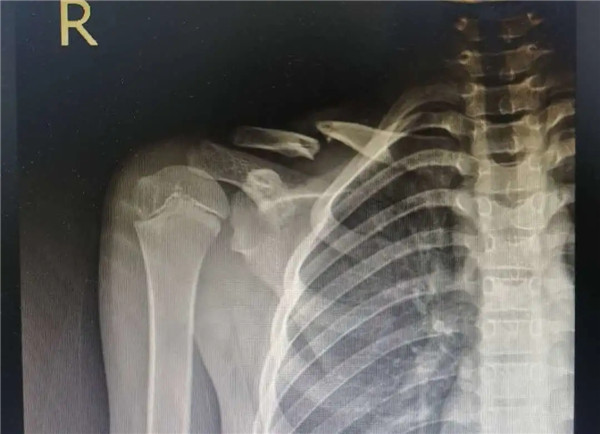

復位前

經(jīng)拍片顯示,洋洋右鎖骨中遠段骨折。查體時,洋洋右肩部腫脹,有壓痛感,右肩關(guān)節(jié)上舉、外展活動受限,建議其入院并接受手術(shù)治療。洋洋媽媽當即辦理了入院手續(xù)。